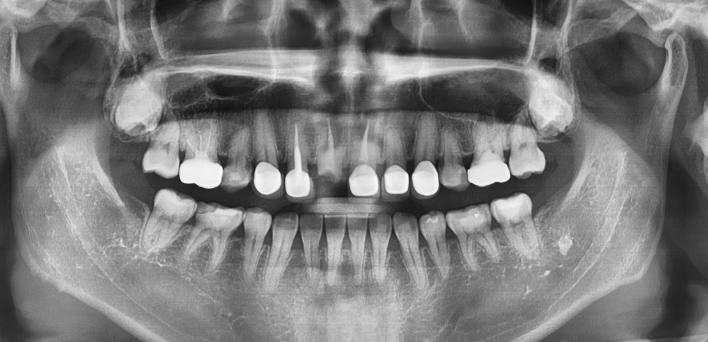

임플란트 : 손 ** 님 (50대)

치아가 있다는게, 아직도 정말 꿈만 같아요.

Before Before

2020.02.30

After After

※ 더서울치과의원은 의료법을 준수하며 위 케이스는 실제 환자의 동의를 얻은 사례로 치료 전, 후가 동일한 환경에서 촬영되었습니다.

환자 케이스에 따라 부작용이 발생할 수 있습니다. 이 부분은 의료진의 충분한 상담과 체크를 통해 예방하고 줄일 수 있습니다.

[임플란트 부작용] 수술 후 관리가 소홀할 경우 출혈, 주위염 등의 부작용이 발생할 수 있어 구강 위생을 철저히 유지하고, 정기적인 검진을 통해 상태를 점검하는 것이 중요합니다.

환자 특징

환자 특징01무치악 상태

환자 특징02수년간 무치악으로 지내심

임플란트가 불가능할것이라

생각하고 내원

위, 아래 6개씩 식립

디지털 풀아치 임플란트